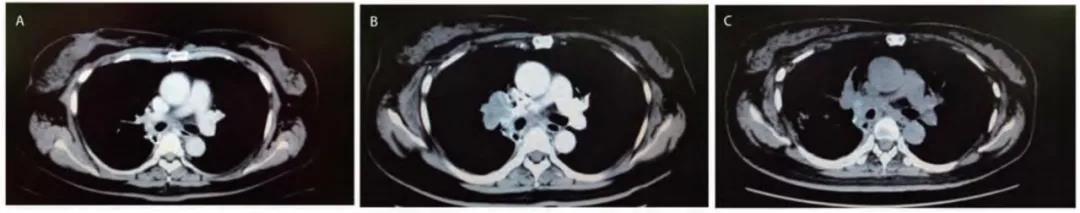

病例简介患者女性,46,因体检发现肝占位1周,于2019年2月就诊于浙江大学医学院附属第二医院。7年前因左乳腺肿物于外院行左乳腺癌改良根治术,术后未行放化疗。&n...